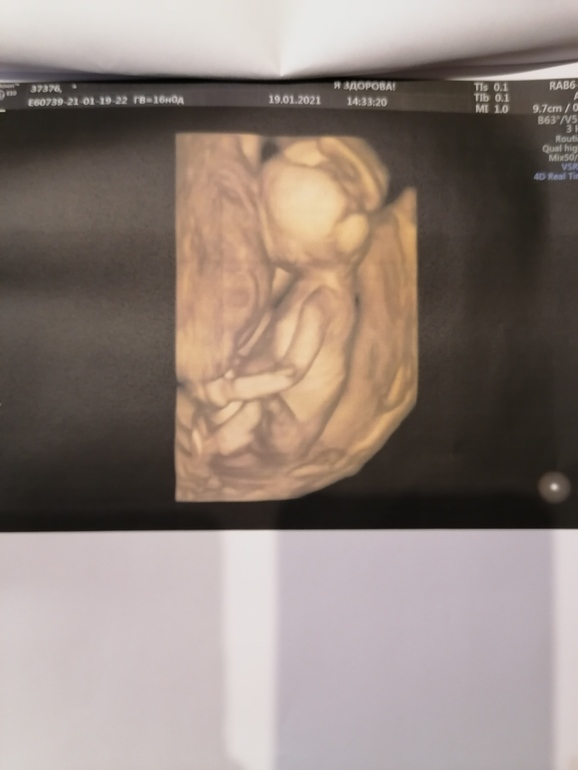

16 недель, фотки, узи у эксперта Пятых Н. С. 🙏🙏🙏👶💙💙💙

Я так счастлива, что с сыночком все хорошо👶🙏🙏🙏. Сидит на попе, прыгает, толкается, ручками машет🥰👶💙💙💙🙏🙏🙏. Шейка моя начала вести себя не айс, опять буду одевать пессарий.

По размерам опережает на неделю🥰

Ну и мой любимый сыночек, предположительно Константин Сергеевич👶💙💙💙🙏🙏🙏

Личико не показывает никак🙈👶